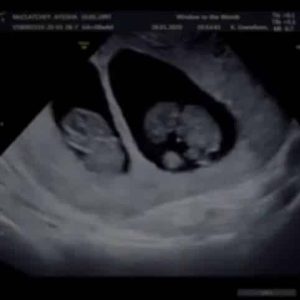

Last Tuesday marked a year ago since our first scan, the first time we ever saw our babies! We waited anxiously, my sickness heightened, we